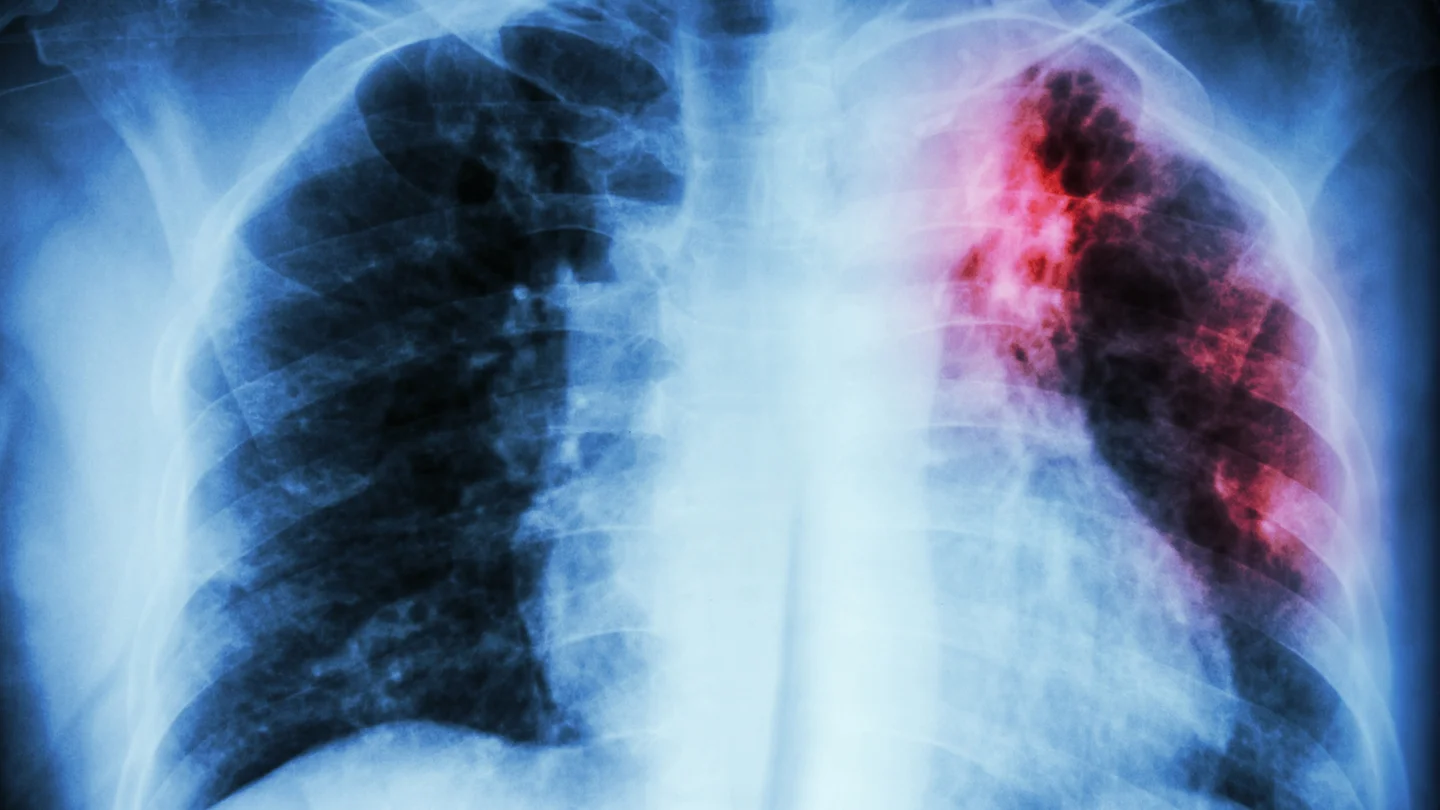

Tuberkulose: Eine Röntgenaufnahme des Brustkorbs. Eine rot-schwarze Verfärbung im linken Lungenflügel weist auf eine Tuberkuloseinfektion hin. Tuberkulose: Eine Röntgenaufnahme des Brustkorbs. Eine rot-schwarze Verfärbung im linken Lungenflügel weist auf eine Tuberkuloseinfektion hin.

Neben dem Erregernachweis gehört zur Diagnostik immer auch eine Röntgenaufnahme der Lunge. Damit können Ärztinnen und Ärzte feststellen, ob Hinweise auf eine Lungentuberkulose vorliegen, die unter Umständen ansteckend sein kann. Anhand der Röntgenaufnahme kann man auch beurteilen, ob die Behandlung einer Lungentuberkulose erfolgreich verläuft. Um Veränderungen an der Lunge genauer beurteilen zu können, kann in einigen Fällen auch eine Computertomografie durchgeführt werden, ein sogenanntes Schichtröntgen.